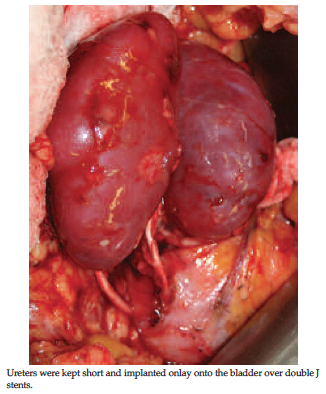

En bloc implantation of small pediatric kidneys was developed to address some of these concerns: using the aorta and inferior vena cava as a vascular conduit to avoid or minimize vascular complications, and transplanting both kidneys together to offset the problem of hyperfiltration.12 The Newcastle en bloc technique developed by Talbot and associates1 is a safe way of implanting a pediatric kidney en bloc. In this technique, the infrarenal aorta and inferior vena cava of the en bloc graft are switched to suprarenal position (Figure 1). This allows one to lower the kidneys into the iliac fossa and implant them with shorter ureters (Figure 2).

Figure 2. En bloc kidneys after implantation